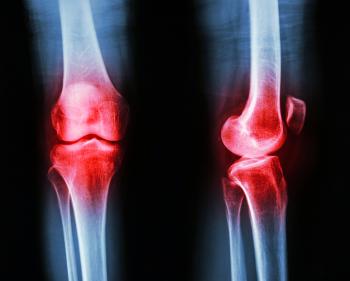

Suferinta pacientilor cu osteoartrita ar putea fi inlaturata cat de curand cu ajutorul descoperirilor celor mai recente ale cercetatorilor in domeniul folosirii celulelor stem.

Succesul este atribuit unei noi proceduri in care sunt utilizate celule stem embrionare, cercetarea fiind realizata de oamenii de stiinta ai Universitatii Manchester din Marea Britanie.

Studiul a fost finantat de Arthritis Research UK . Studiul demonstreaza felul in carenoul protocol a fost folosit sa creasca si sa transforme celulele stem embrionare umane in celule cartilaginoase.

Aceasta lucrare reprezinta un pas important in tratarea daunelor provocate cartilajelorcu ajutorul folosirii  celulelor stem embrionare pentru a forma tesut nou, chiar daca cercetarea este inca in faza experimentala.